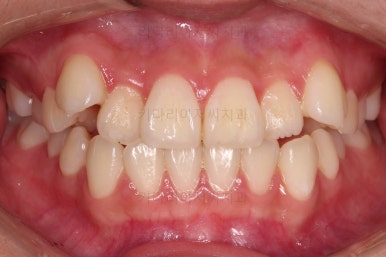

오늘 연산동교정치과 키다리아저씨치과에서 소개해 드릴 환자분은 덧니때문에 교정하고자 하셨던 분입니다.

다만, 웃을 때 치열이 삐뚤다 보니 활짝 못 웃게 되고 드러나는 치열이 심미적이지 못하네요.

입 안을 보면 밑에 치열이나 다른 부분은 비교적 양호한데 유달리 윗니 송곳니만 위치가 좋지 못하네요.

비발치

이번 환자분은 보기에는 송곳니가 덧니라 많이 삐뚤어 있는 것 같지만 치료는 비발치, 즉 발치 없이 진행했는데요.

자칫하면 비발치 시 입이 튀어나오는 경우가 있어요.

삐뚤다는 건 자리가 부족하다는 뜻인데 부족한 자리를 확보 안해주고 억지로 가지런하게 하다보면 치아가 앞으로 튀어나오게 되거든요.

그래서 비발치로 하더라도 본인이 만족할만한 수준까지 입이 나오지 않도록 미니스크류를 병행해서 사용하여 통째로 뒤로 당겨주기로 했습니다.